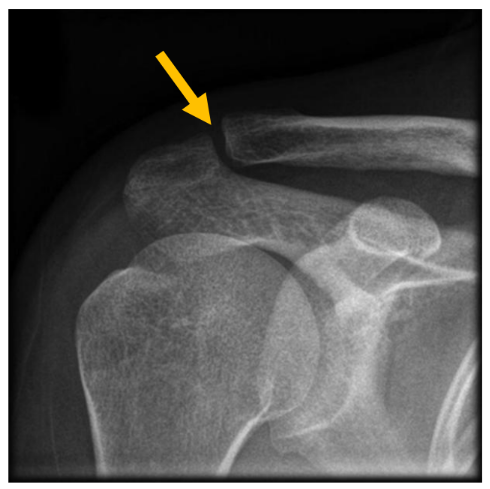

What is an acromioclavicular joint sprain?

You have a sprain (partial disruption of ligament fibres) of the joint between the shoulder blade and collar bone.